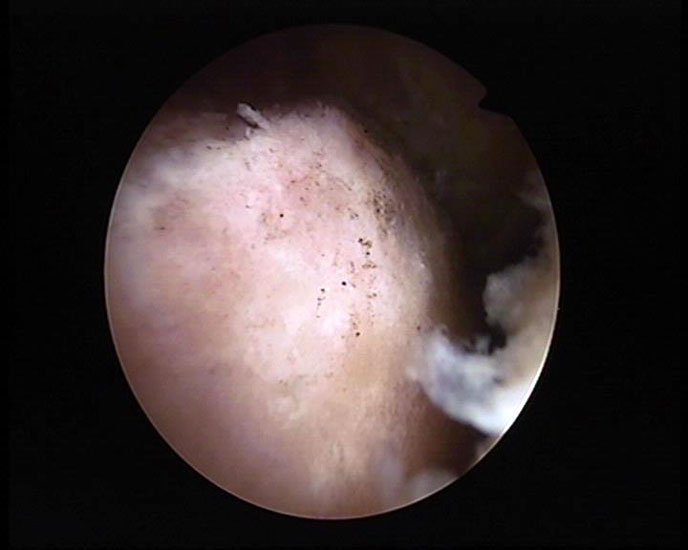

Abbildung 5-7, Video 2

Zunächst wird die Bursektomie (Abb. 5: gerötete Bursa subachillea; C=Calcaneus, B=Bursa, AS=Achillessehne) mit der Radiofrequenzsonde durchgeführt und die Haglundexostose dargestellt. Alternativ kann die Bursektomie mit einem Shaver durchgeführt werden. Hierbei sollte der Ansatz der Achillessehne kaudal einsehbar sein (Abb. 6: C=Calcaneus, AS=Achillessehne) und unbedingt die gesamte mediolaterale Ausdehnung der posterioren Calcaneusfläche erfasst werden (Abb. 7). Häufig liegen Anteile der Exostose weit medial und/oder lateral und werden übersehen.